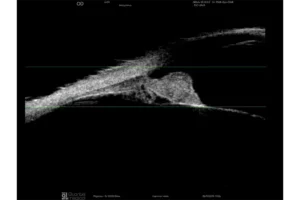

De sondes B15, B20-5A en UBM zijn uitgerust met een IMUv®-bewegingssensor die essentiële real-time informatie biedt, zoals:

- De positie van de sonde op het oog

- De visualisatie van het waargenomen gebied

Dit helpt de operator om onderzoeksgebieden eenvoudiger en sneller te identificeren. Deze technologie is gepatenteerd en exclusief voor Quantel Medical.

- Exclusieve IMUv™-bewegingssensor maakt het mogelijk om de ultrasone bundel in real-time in het oogdiagram te lokaliseren.